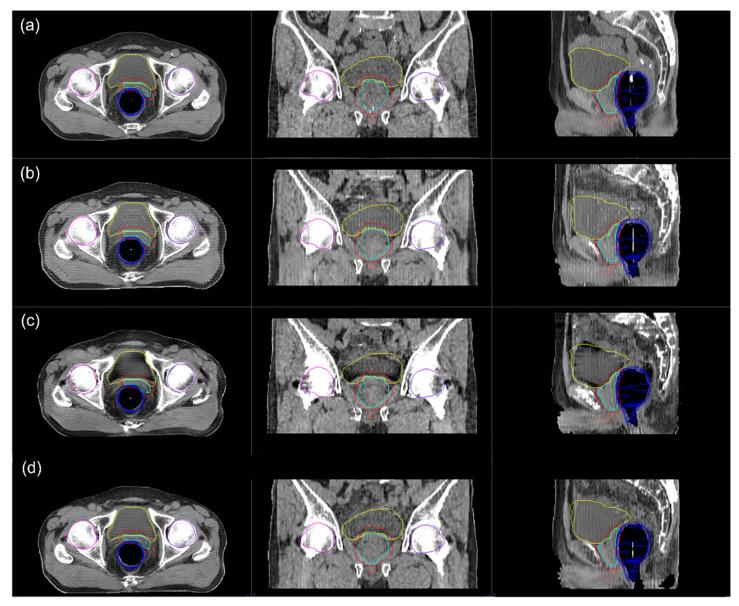

We aimed to evaluate and compare the qualities of synthetic computed tomography (sCT) generated by various deep-learning methods in volumetric modulated arc therapy (VMAT) planning for prostate cancer. Simulation computed tomography (CT) and T2-weighted simulation magnetic resonance image from 113 patients were used in the sCT generation by three deep-learning approaches: generative adversarial network (GAN), cycle-consistent GAN (CycGAN), and reference-guided CycGAN (RgGAN), a new model which performed further adjustment of sCTs generated by CycGAN with available paired images. VMAT plans on the original simulation CT images were recalculated on the sCTs and the dosimetric differences were evaluated. For soft tissue, a significant difference in the mean Hounsfield unites (HUs) was observed between the original CT images and only sCTs from GAN ( = 0.03). The mean relative dose differences for planning target volumes or organs at risk were within 2% among the sCTs from the three deep-learning approaches. The differences in dosimetric parameters for D and D from original CT were lowest in sCT from RgGAN. In conclusion, HU conservation for soft tissue was poorest for GAN. There was the trend that sCT generated from the RgGAN showed best performance in dosimetric conservation D and D than sCTs from other methodologies.

摘要

我们旨在评估和比较在前列腺癌容积调强弧形放疗(VMAT)计划中,各种深度学习方法生成的合成计算机断层扫描(sCT)的质量。通过三种深度学习方法,即生成对抗网络(GAN)、循环一致生成对抗网络(CycGAN)和参考引导循环一致生成对抗网络(RgGAN,一种利用可用配对图像对CycGAN生成的sCT进行进一步调整的新模型),使用113例患者的模拟计算机断层扫描(CT)和T2加权模拟磁共振图像来生成sCT。在sCT上重新计算原始模拟CT图像上的VMAT计划,并评估剂量学差异。对于软组织,在原始CT图像与仅来自GAN的sCT之间观察到平均亨氏单位(HU)存在显著差异(P = 0.03)。在三种深度学习方法生成的sCT中,计划靶区或危及器官的平均相对剂量差异在2%以内。RgGAN生成的sCT与原始CT相比,D95和D2的剂量学参数差异最小。总之,GAN生成的软组织HU保留最差。有趋势表明,与其他方法生成的sCT相比,RgGAN生成的sCT在剂量学保留D95和D2方面表现最佳。